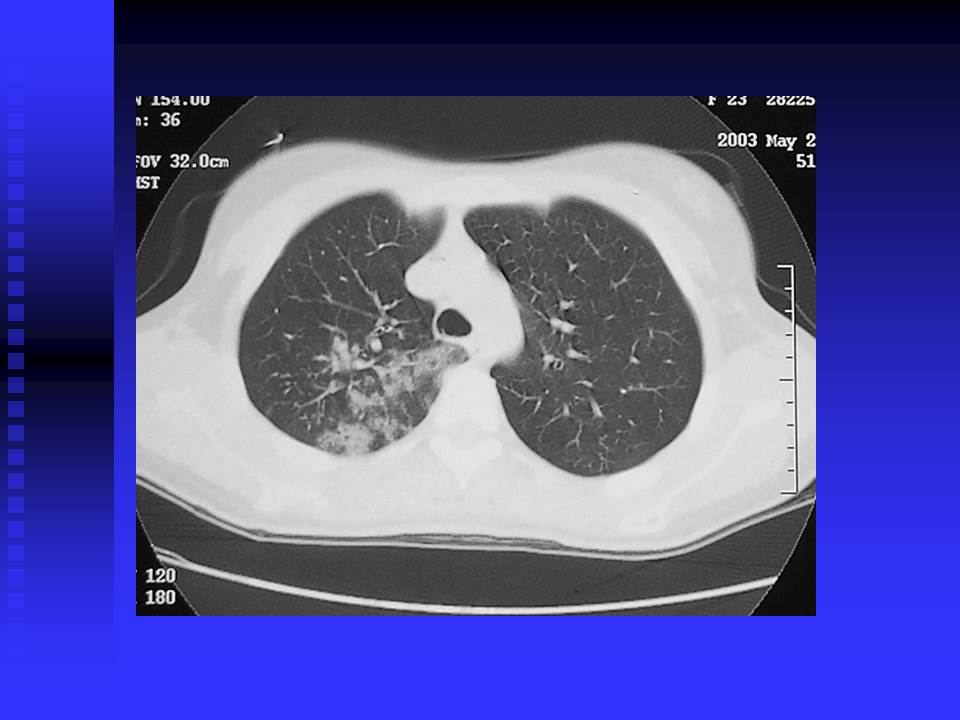

【PPT】严重急性呼吸综合征的影像鉴别诊断